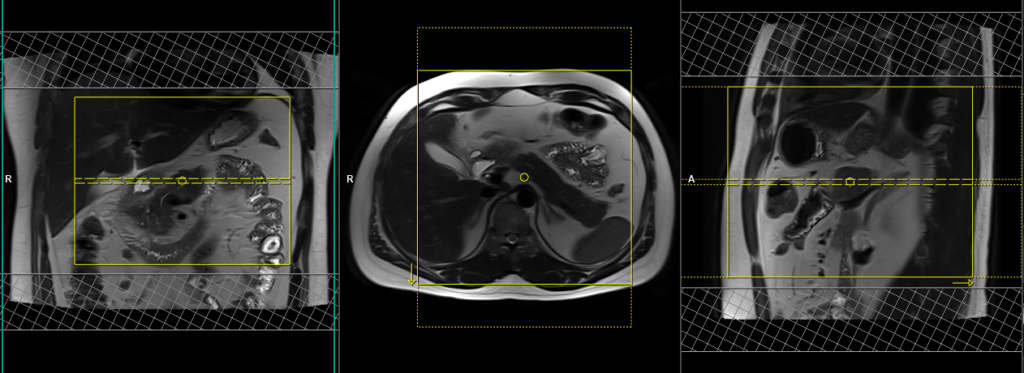

T1 VIBE DIXON 3mm axial BH pre GD(In-opposed phase and water sat)

Plan the axial slices on the coronal breath-hold images and position the block horizontally across the abdomen as shown. Verify the positioning in the other two planes. Establish an appropriate angle in the sagittal plane, aligning it horizontally across the abdomen. The slices must be sufficient to cover the entire pancreas, starting one inch above the pancreatic tail and extending down to the C loop of the duodenum. The phase direction should be from right to left to minimize ghosting artifacts from the anterior abdominal wall. Use phase oversampling to prevent wrap-around artifacts. Consider adding saturation bands at the top and bottom of the block to minimize artifacts caused by fat signal, arterial pulsation, and breathing. Instruct the patient to hold their breath during image acquisition.

Planning must be done in the breath hold HASTE coronal because the diaphragm will push down the upper abdominal organs during inhalation and change the position of pancreas from the initial localizer scans.

Parameters

TR 6-7 | TE 2.39 4.77 | FLIP 10 | NXA 1 | SLICE 3 MM | MATRIX 288×256 | FOV 250-280 | PHASE A>P | OVERSAMPLE 20% | BH YES |